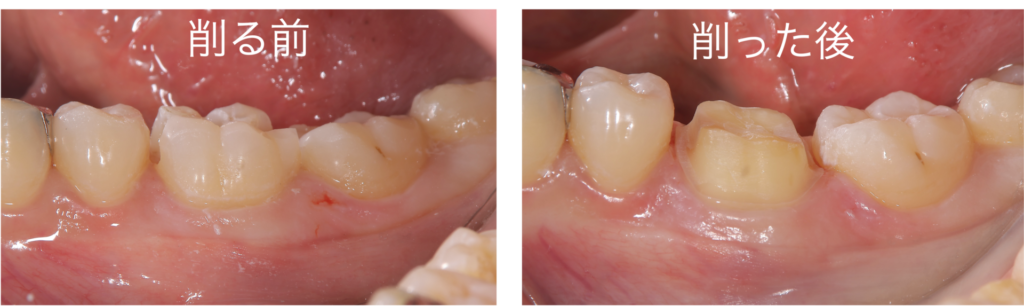

実際に被せ物(クラウン)を装着した方の、歯の削り方も見てみましょう

左の写真は虫歯をとった後であり、歯の大部分が健全な状態です。しかしながら、外れない被せ物(クラウン)を作製する際には、右の写真のように削ってしまう必要があります

正直、このように歯の健康な部分を削ってしまうのはもったいなくないでしょうか・・・